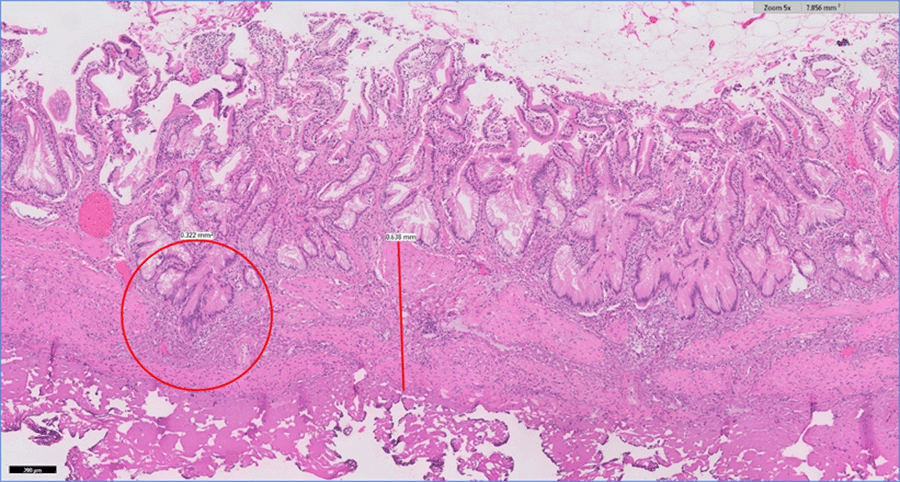

The patient's physical exam was unremarkable. He appeared well-developed, with no acute distress. He did not have scleral icterus. His abdomen was soft, nondistended, nontender, with a negative Murphy's, and no masses, hernia, or scars. BMI 35.14 kg/m2. After carefully discussing the risks and benefits of surgical intervention, the patient underwent laparoscopic cholecystectomy. The procedure was performed without complication, and no abnormalities of the gallbladder or surrounding structures were encountered intraoperatively. The patient was evaluated postoperatively at two-week follow-up and reported a complete resolution of his symptoms. He noted continued pain relief and improved food tolerance at four-week and five-month assessments. His surgical pathology was significant for chronic cholecystitis, as illustrated in Figure 1.

Figure 1. Pathologic Findings of Chronic Cholecystitis at 5x Magnification. Published With Permission

Gallbladder wall measuring 0.3 cm with apparent thickening of the muscularis marked by line. Presence of Rokitansky-Aschoff sinuses circled.

While the pathophysiology of biliary hyperkinesia is poorly understood, one proposed etiology is that patients with greater CCK production or density/activity of CCK receptors trigger intense contraction of the gallbladder, causing elevated intraluminal pressure, pain, and inflammation with stimulation.5-6,9 As observed in our patient, many studies have documented chronic cholecystitis on surgical pathology.3-9 Thickening of the tunica muscularis may additionally be noted.5 A summary of results from the current literature is presented in Table 1.